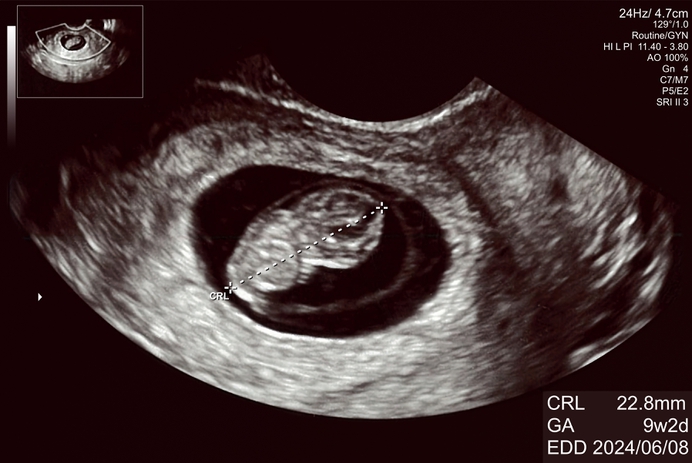

Een ongeboren kindje met negen weken zwangerschap. De schedel wordt al zichtbaar. De abortuslobby doet echter alsof het kindje slechts een stuk weefsel is.

Het kan niet waar zijn dat de Nederlandse overheid zoveel geld uitgeeft aan een organisatie die samen met het Nederlands Genootschap van Abortusartsen, vrouwen zo ontzettend misleidt. Wanneer een vrouw later weer zwanger raakt, het kindje dit keer wil houden en ze gaat met negen weken zwangerschap naar de verloskundige waar ze mee kan kijken met de echo, dan heeft zij een probleem. Dan ziet zij dat de afbeelding van Fiom een valse voorstelling was. Wat voor trauma zal de vrouw dan oplopen?